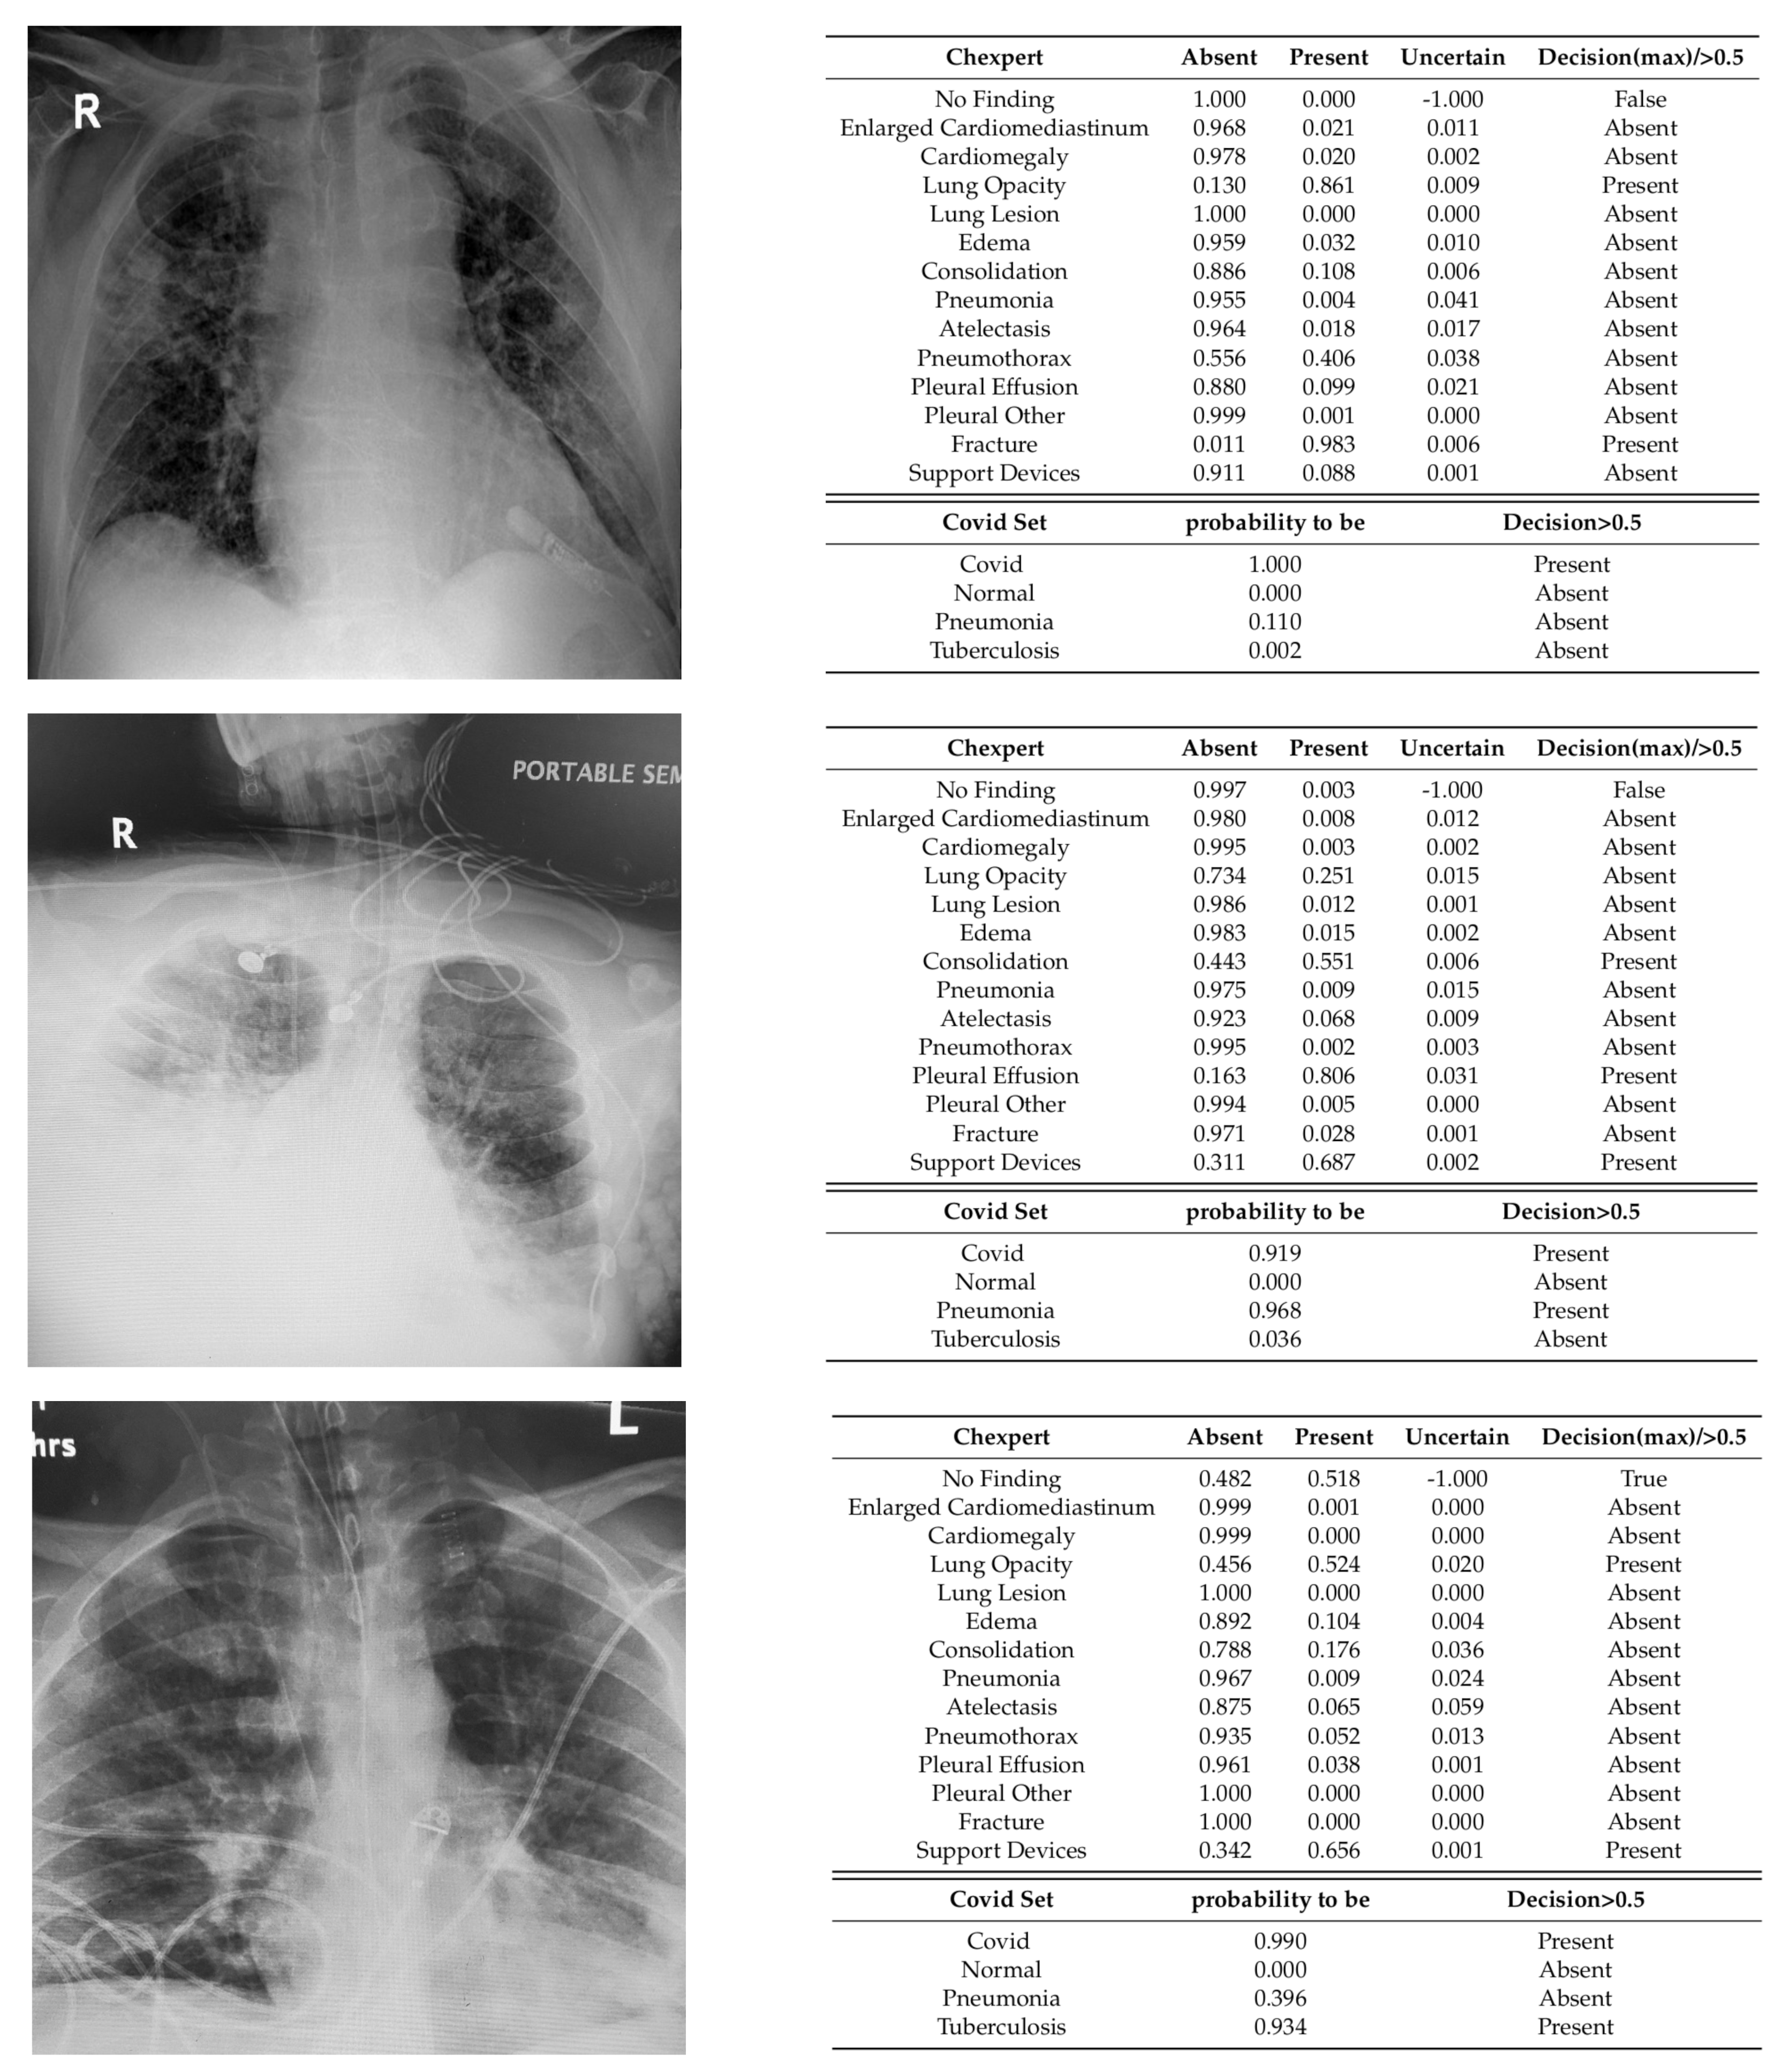

3.2.3. Qualitative Analysis